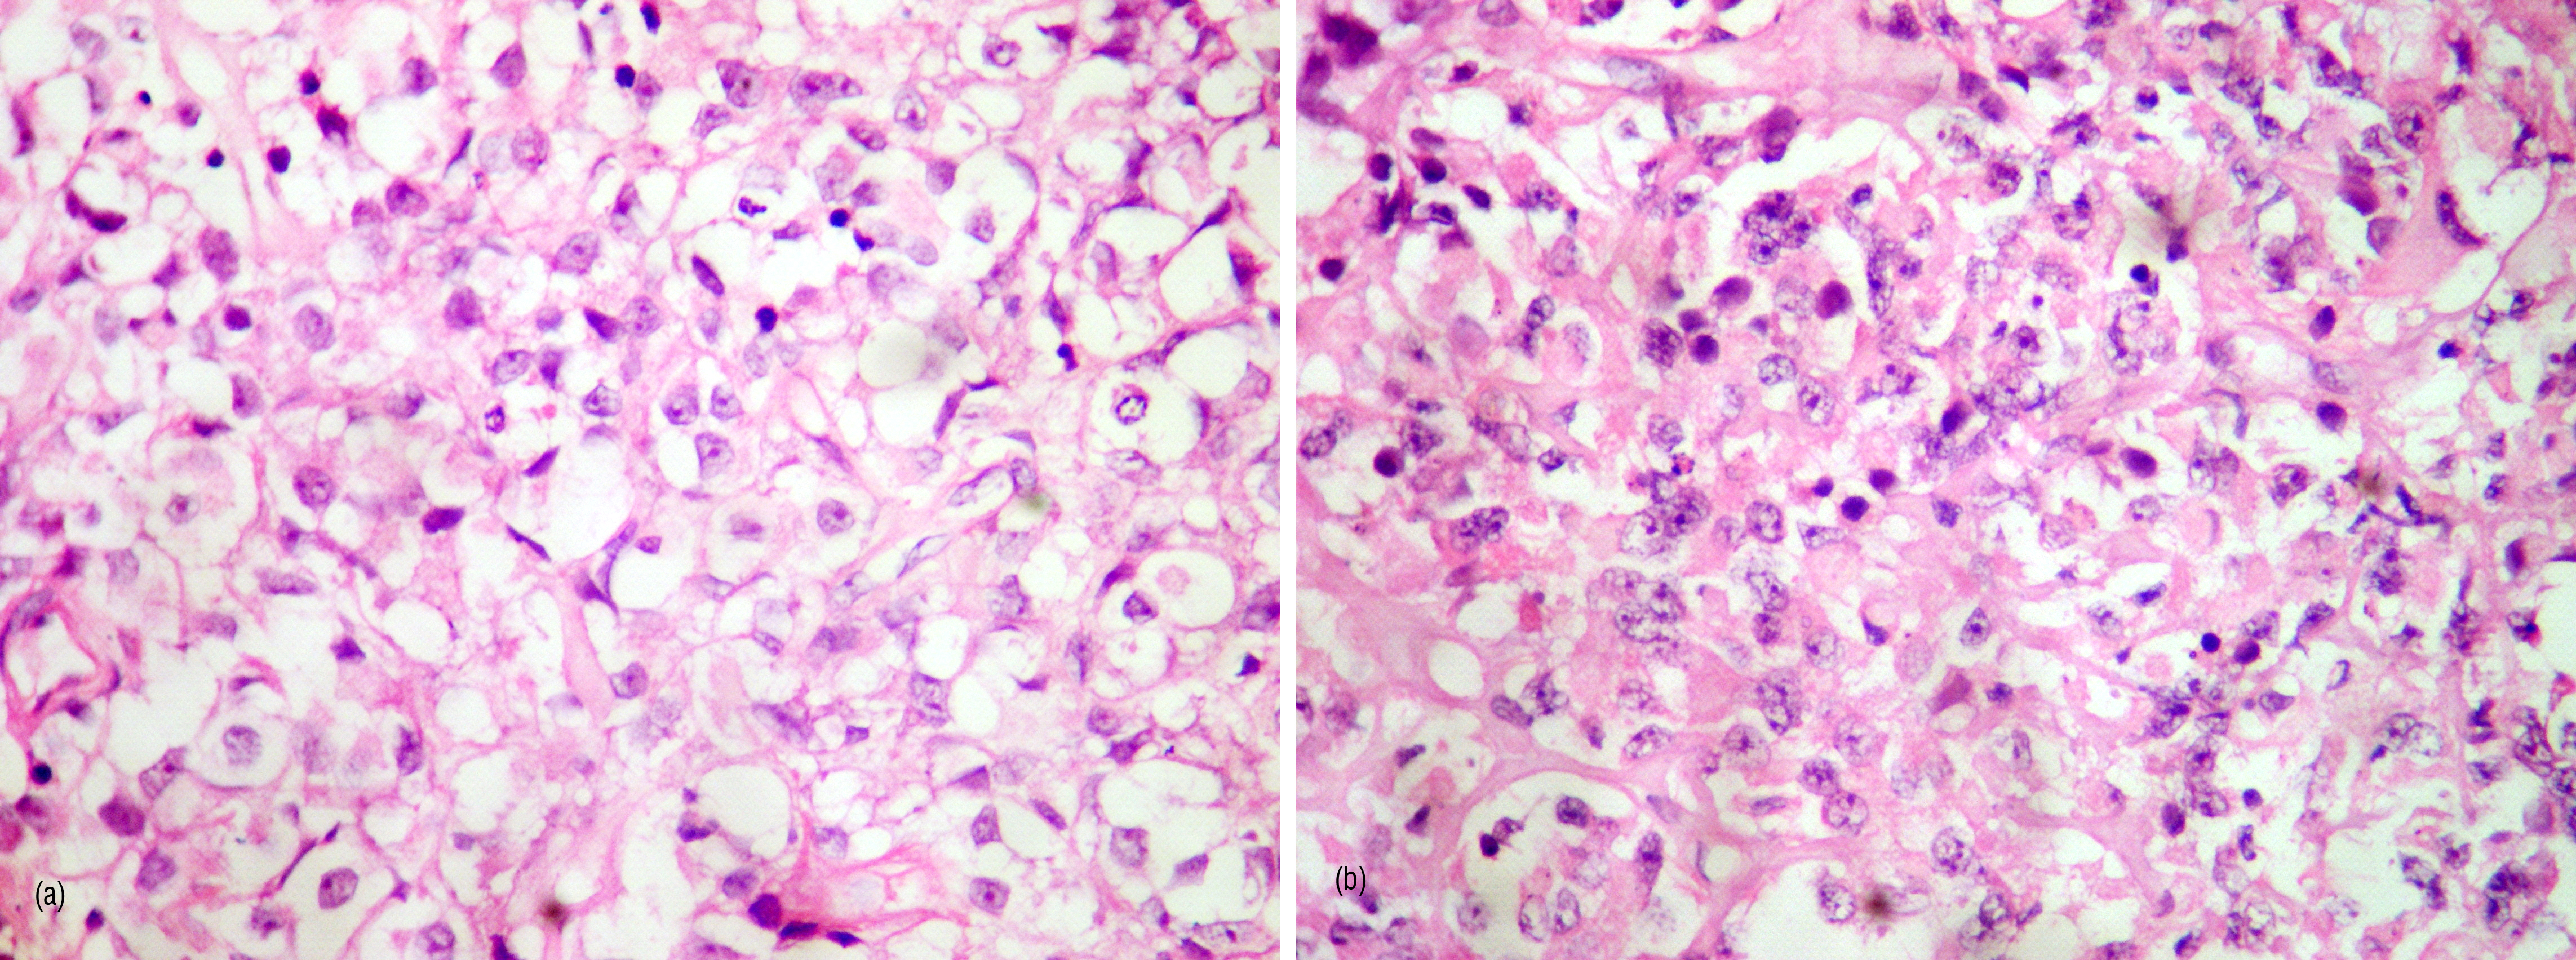

Patient underwent right pterional craniotomy and subtotal resection of suprasellar lesion. Per-operatively there was grayish firm mildly vascular lesion with calcification in suprasellar region with compression of optic apparatus. Post operative histopathology showed moderately cellular neoplasm with nuclear atypia, hyperchromasia. Several cells had rhabdoid like morphology. Foci of micronecrosis were present. It was reported as atypical cellular tumour with rhabdoid morphology.

Figure 2a,b: Cellular neoplasm with multiple rhabdoid cells.

Immunohistochemistry showed glial fibrillary acidic protein (GFAP), desmin & chromogranin negativity, synaptophysin had faint cytoplasmic positivity, epithelial membrane antigen showed focal positivity in clear cells but was negative in rhabdoid cells. Mib-1 index was positive in upto 25% of cells. INI -1 staining was lost in tumour cells but was retained in endothelial cells.